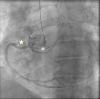

Figure 1.

Figure 1.. Cardiac catheterisation with right coronary artery marked by green outlined star and left coronary artery marked by asterisk symbol